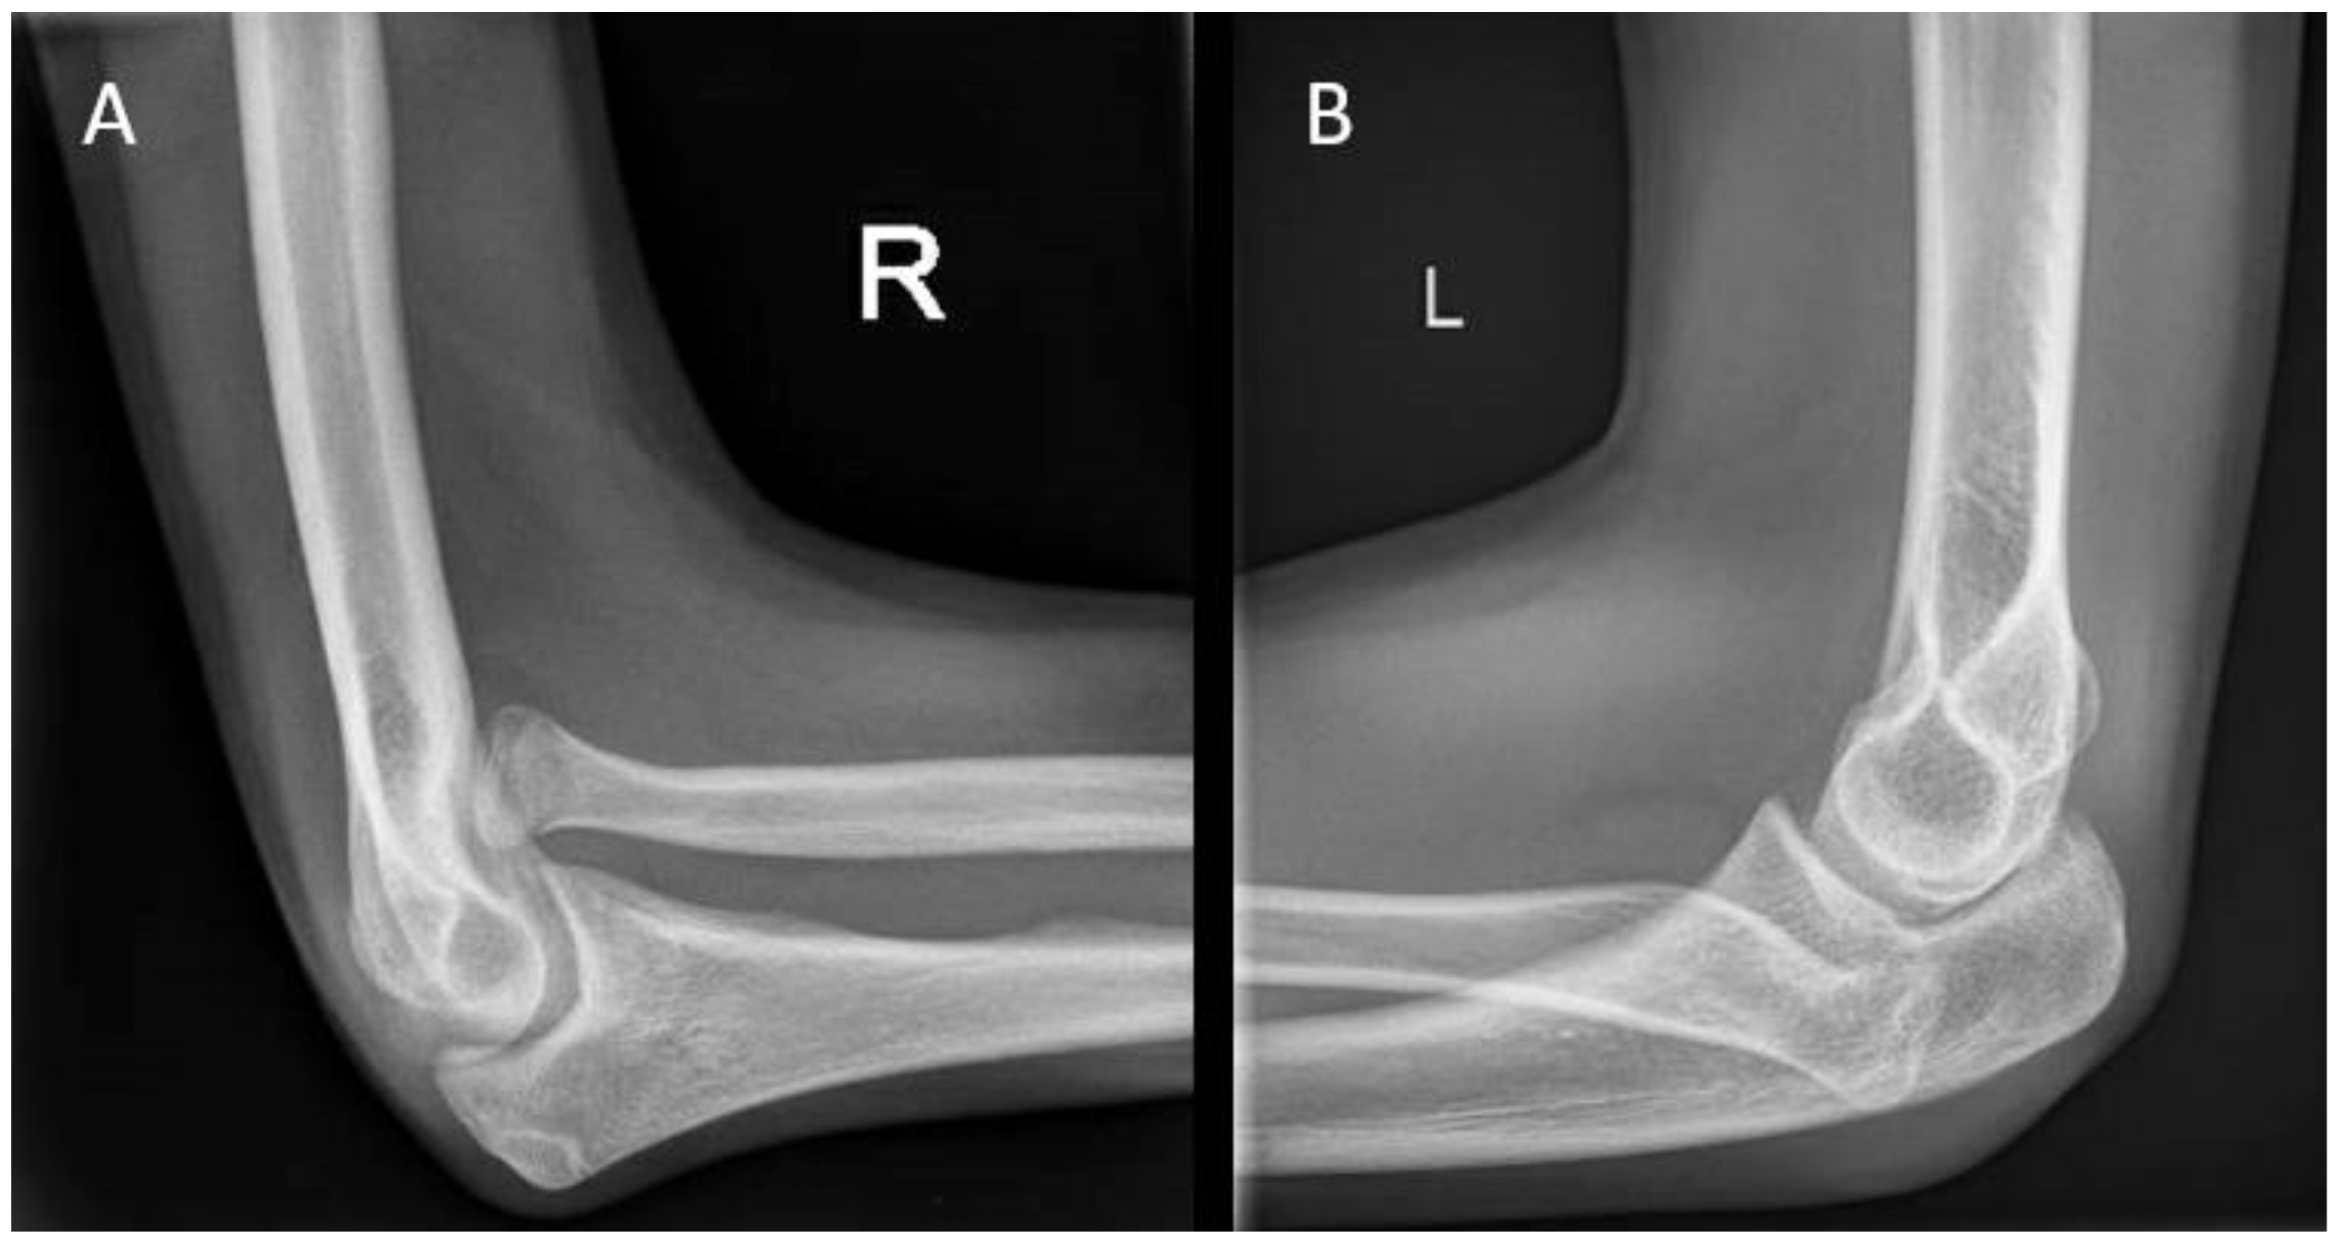

During visual inspection, the patient is placed in front of the examiner, standing in the anatomical position with both elbows fully extended (Figure 1). The carrying angle is measured best in a standing patient with arms in the anatomical position, with arms fully extended and wrists fully supinated. The carrying angle is the angle deviated from the line parallel to the humerus and the forearm. The carrying angle is usually greater in women, with an average of 15–20 degrees. In men, the carrying angle is, on average, 10–15 degrees [5,6,7]. Therefore, the carrying angle is compared best with the contralateral side. A physiological change in the carrying angle from valgus to varus can be observed as the patient flexes the elbow and supinates the forearm [8]. Assessment of the carrying angle is therefore performed in the same amount of flexion and rotation of both arms to optimize adequate comparison. In most female patients and children, a slight hyperextension of the elbow of 0 to 10 degrees is physiological [9]. Deformities in the sagittal plane are measured with the humerus in 90 degrees anteflexion and by flexing and extending the elbow with the forearm in a supinated position.

Cubitus varus is most often seen as late sequela after a distal humerus fracture (Figure 1B). The current stance in the literature is that it is caused by malunion of a humeral fracture rather than a growth arrest. The most common type of distal humerus fracture in children is the supracondylar fracture [25]. They are classified using the Gartland type classification, ranging from type I to type III, depending on the amount of posterior displacement of the capitellum and the intactness of the posterior humeral cortex [26]. Cubitus varus, however, results from displacement or comminution in the coronal plane. These injuries are often overlooked or difficult to judge on standard radiographs. Therefore, in type II and type III fractures, an oblique view may be helpful in identifying minimally displaced fractures [27]. Rotational malalignment can be difficult to assess radiographically. A high index of suspicion for rotational malalignment is required in cases of posteromedial displacement. These cases may also lead to a higher Baumann angle and hence combined cubitus varus deformity [28]. If missed or left untreated, the malunion leads to a progressive angular deformity in the coronal plane. The result at patient presentation is often a painless varus deformity evident at visual inspection that may not always be accompanied by limitations in ROM [25]. Although diagnosis is usually based on clinical evaluation alone, measuring the radiological Baumann angle compared to the contralateral side may give a more accurate measure of the extent of the deformity.

Figure 1. (A) Visual inspection of the carrying angle of the elbow in a 10-year-old girl showing a unilateral cubitus varus on the right side. (B) Anteroposterior radiographic views of the elbow with the unaffected contralateral side for comparison.